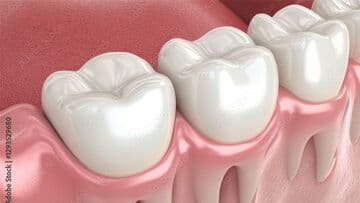

CT

3次元的に頭蓋骨の解剖学的形態を詳細に把握することで、インプラントの手術をより安全に行うための診断ツールです。現在、インプラント治療ではCT撮影は必須とされています。

ガイデットサージェリー

CT画像とお口の中をスキャニングしたデータをマッチングさせ、インプラントを正確な位置・角度・深さに埋入する補助器具のことです。難しい位置でのインプラントの埋入でもガイドを用いることで、安全に治療を遂行することができます。